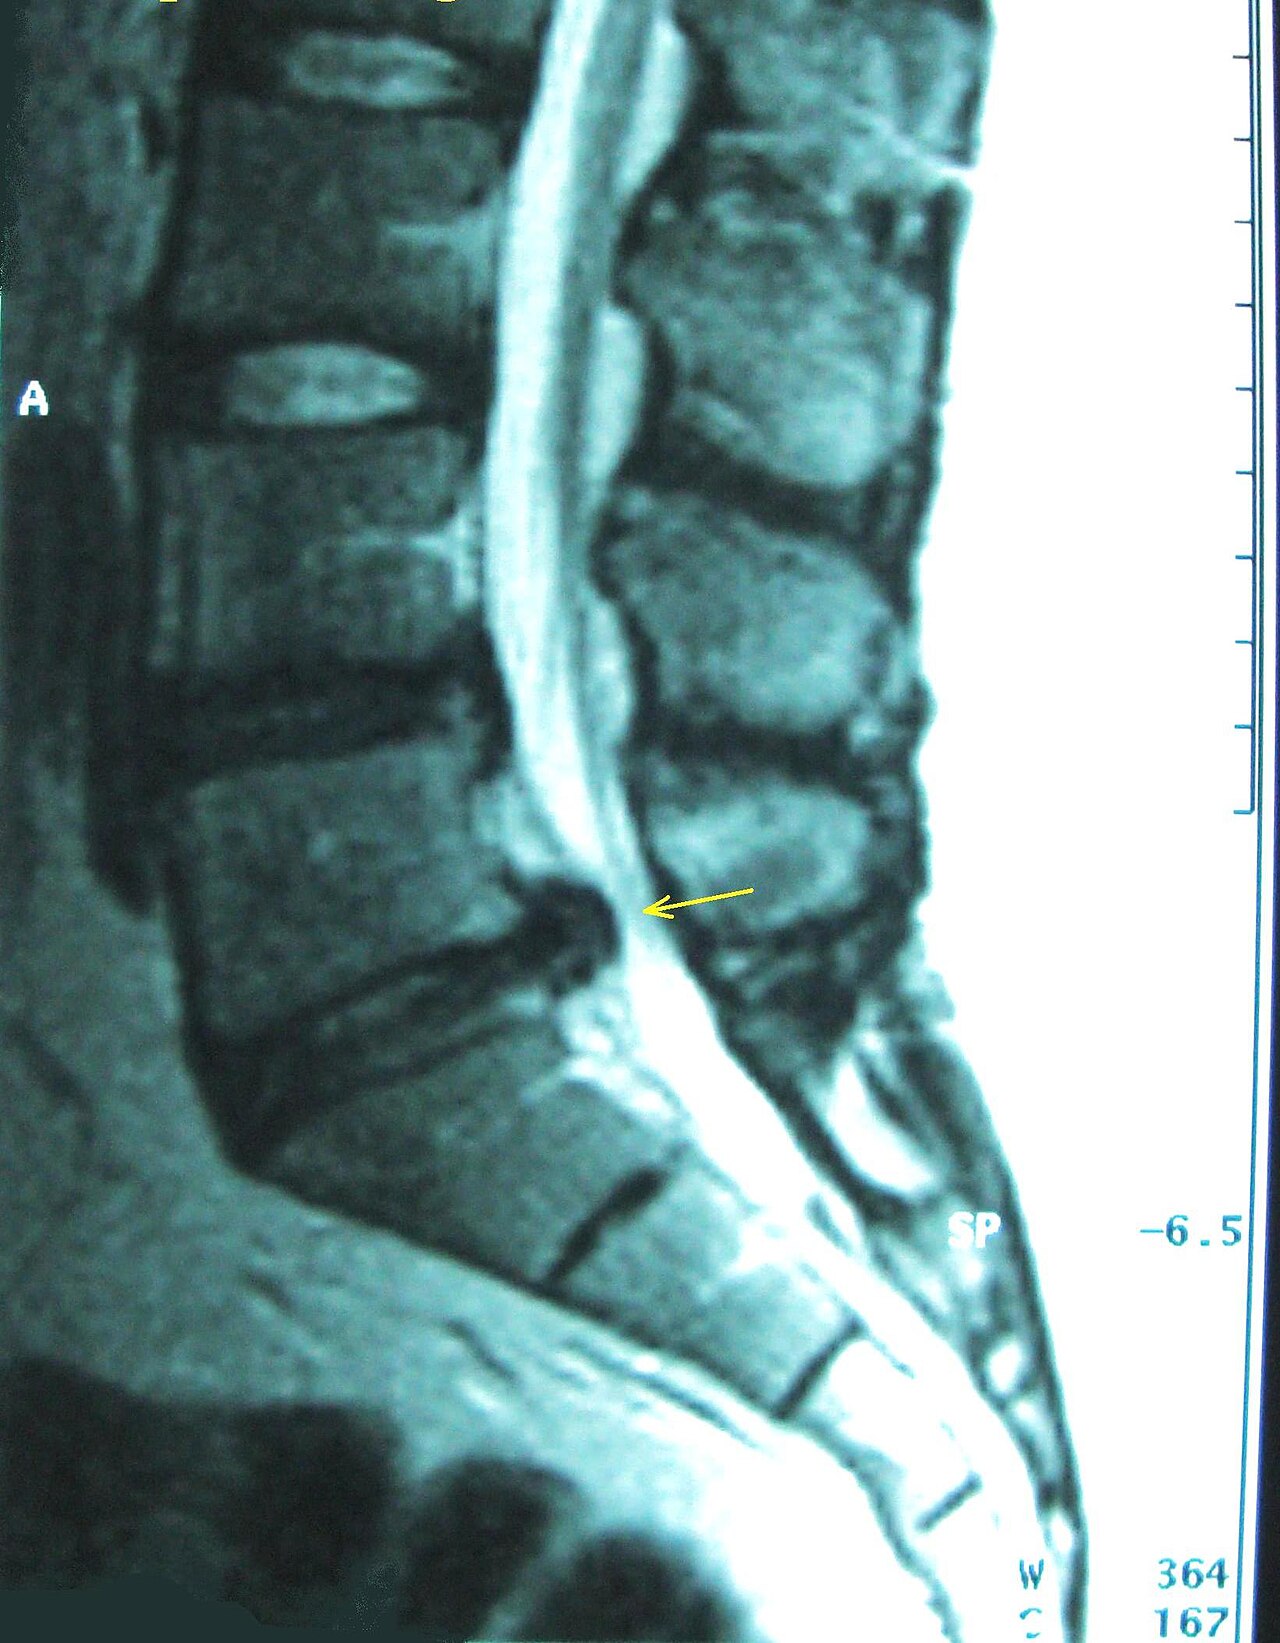

L4-L5 posterolateral disc herniation compressing the L5 nerve root with disc desiccation, annular tear, and...

Lumbar spinal stenosis with ligamentum flavum hypertrophy, facet joint arthropathy, disc bulge, and narrowed central canal